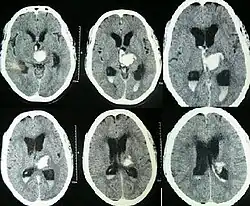

Hemorragia intracerebral espontânea com hidrocefalia na tomografia computadorizada[6]

Tanto a angiografia por tomografia computadorizada (ATC) como a angiografia por ressonância magnética (ARM) demonstraram ser efetivas no diagnóstico de malformações vasculares intracranianas após a hemorragia intracerebral.[13] Com tanta frequência, um angiograma de tomografia computadorizada será realizado para excluir uma causa secundária de hemorragia[14] ou para detectar um "sinal local".

A hemorragia intraparenquimatosa pode ser reconhecida na tomografia computadorizada porque o sangue aparece mais brilhante do que outro tecido e é separado da mesa interna do crânio por tecido cerebral. O tecido que envolve um sangramento é muitas vezes menos denso do que o resto do cérebro por causa do edema e, portanto, aparece mais escuro na tomografia computadorizada.[14]